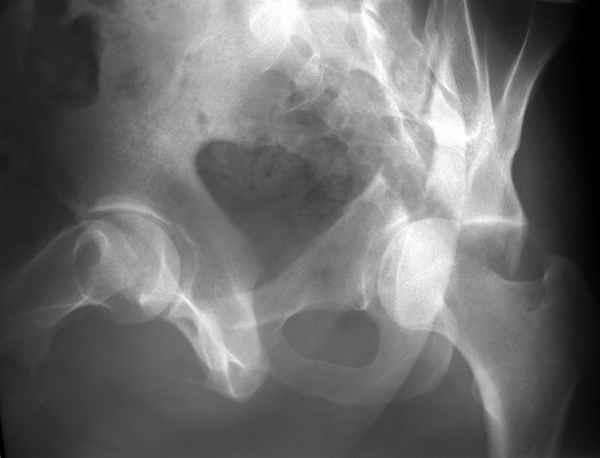

Повреждение сложное. DS:Ротационно нестабильное повреждение таза, перелом боковой массы крестца,ипсилатеральный высокий двухколонный перелом вертлужной впадины с центральным смещением сустава, двусторонний перелом лонных и седалищных костей.

При оперативном лечении прогноз относительно благоприятный. Показано два доступа - чрезвертельный Y-образный и затем синтез лонных костей двумя пластинами.

Запасной вариант вместо второго доступа - передняя рама аппарата, но он не гарантирует хорошую анатомию.

Консервативное лечение бесперспективно с точки зрения дальнейшего качества жизни.

Перед операцией необходимо скелетное вытяжение по оси бедра 10-12 кг.

Вытяжение за вертл не только бессмысленно, но и опасно. Гамак не нужен.